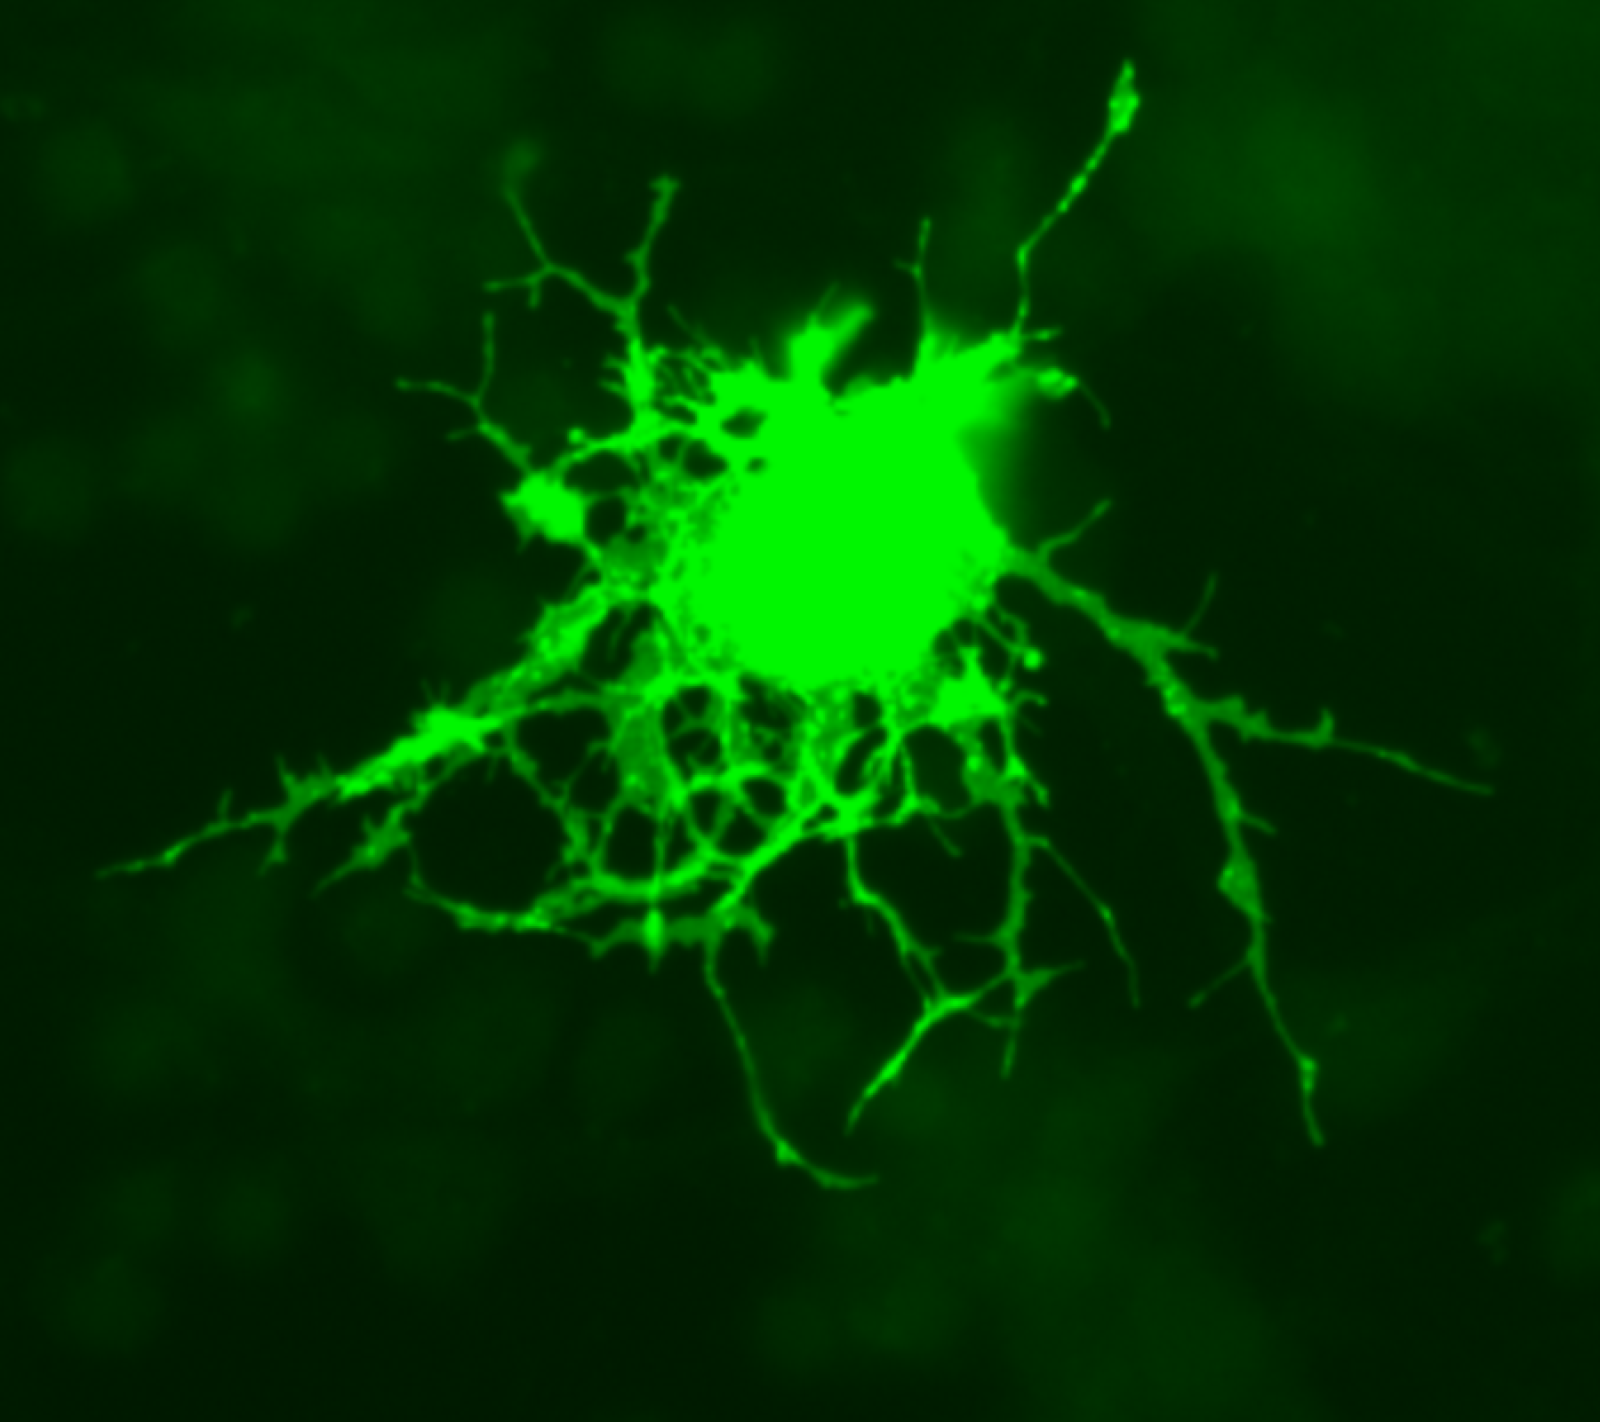

Oligodendrocita, modificato con GFP (Green Fluorescent Protein) - Credit: photo by Jurjen Broeke - Wikimedia - Pubblico dominio

Il nostro cervello è un organo incredibilmente complesso, formato da molti miliardi di cellule. Tra queste, i neuroni sono responsabili della trasmissione dell’impulso nervoso, mentre altre cellule, chiamate oligodendrociti, avvolgono i lunghi filamenti dei neuroni a formare la guaina mielinica, una struttura isolante che avvolgendosi strettamente ai prolungamenti dei neuroni, permette un’efficiente propagazione degli impulsi nervosi da una cellula all’altra. Nella sclerosi multipla, una malattia degenerativa demielinizzante, questa guaina viene danneggiata, rendendo la trasmissione nervosa più lenta e difficoltosa. Viene anche classificata come malattia autoimmune perché è lo stesso sistema immunitario del soggetto che non riconoscendo la mielina come componente essenziale della cellula innesca un processo di autodistruzione. Per questo motivo, gli individui affetti da sclerosi multipla iniziano a manifestare tremori, spasmi muscolari, affaticamento, che in molti casi può peggiorare fino a portare alla paralisi degli arti.